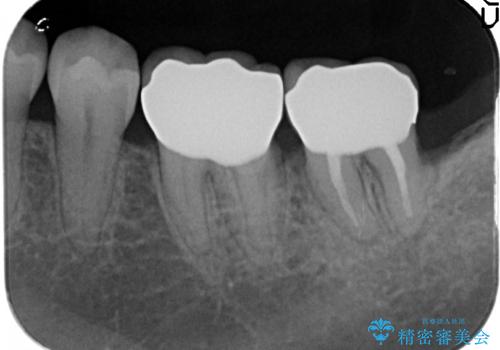

歯周外科手術終了後、歯茎の回復を待ち左下6、7ともにオールセラミッククラウン(スタンダード)による補綴を行いました。

今回用いたオールセラミッククラウンはジルコニアフレームという白い素材の上にセラミックを盛っているため、審美性が非常に高いのが特徴です。

また、ジルコニアは人工ダイヤモンドの材料にも使われているほど高い強度を持っており、そのためオールセラミッククラウンは審美性だけでなく、奥歯やブリッジの補綴も可能とするクラウンです。